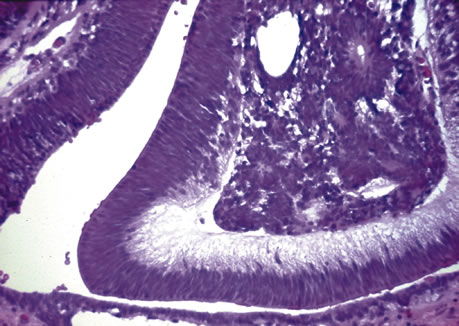

Medulloepithelioma

Medulloepithelioma is classified as benign or malignant and may be teratic. Histologically, benign medulloepithelioma is usually composed of multi-layered sheets or cords of immature neuroepithelial cells (Fig. 12). The presence of poorly differentiated neuroblastic cells resembling neuroblastoma, significantly increased pleomorphism, mitotic activity, sarcomatous areas resembling chondrosarcoma or rhabdomyosarcoma (Fig. 13), and invasion of the uvea or cornea have been listed as criteria for malignancy.83,84 When elements such as hyaline cartilage or skeletal muscle are present, the tumor is designated teratic but may also be classified as benign or malignant based on the previously listed cytologic criteria.

Fig. 12. Medulloepithelioma. The tumor displays cords and tubular structures made up of medullary epithelium. (Hemotoxylin-eosin ×180.)